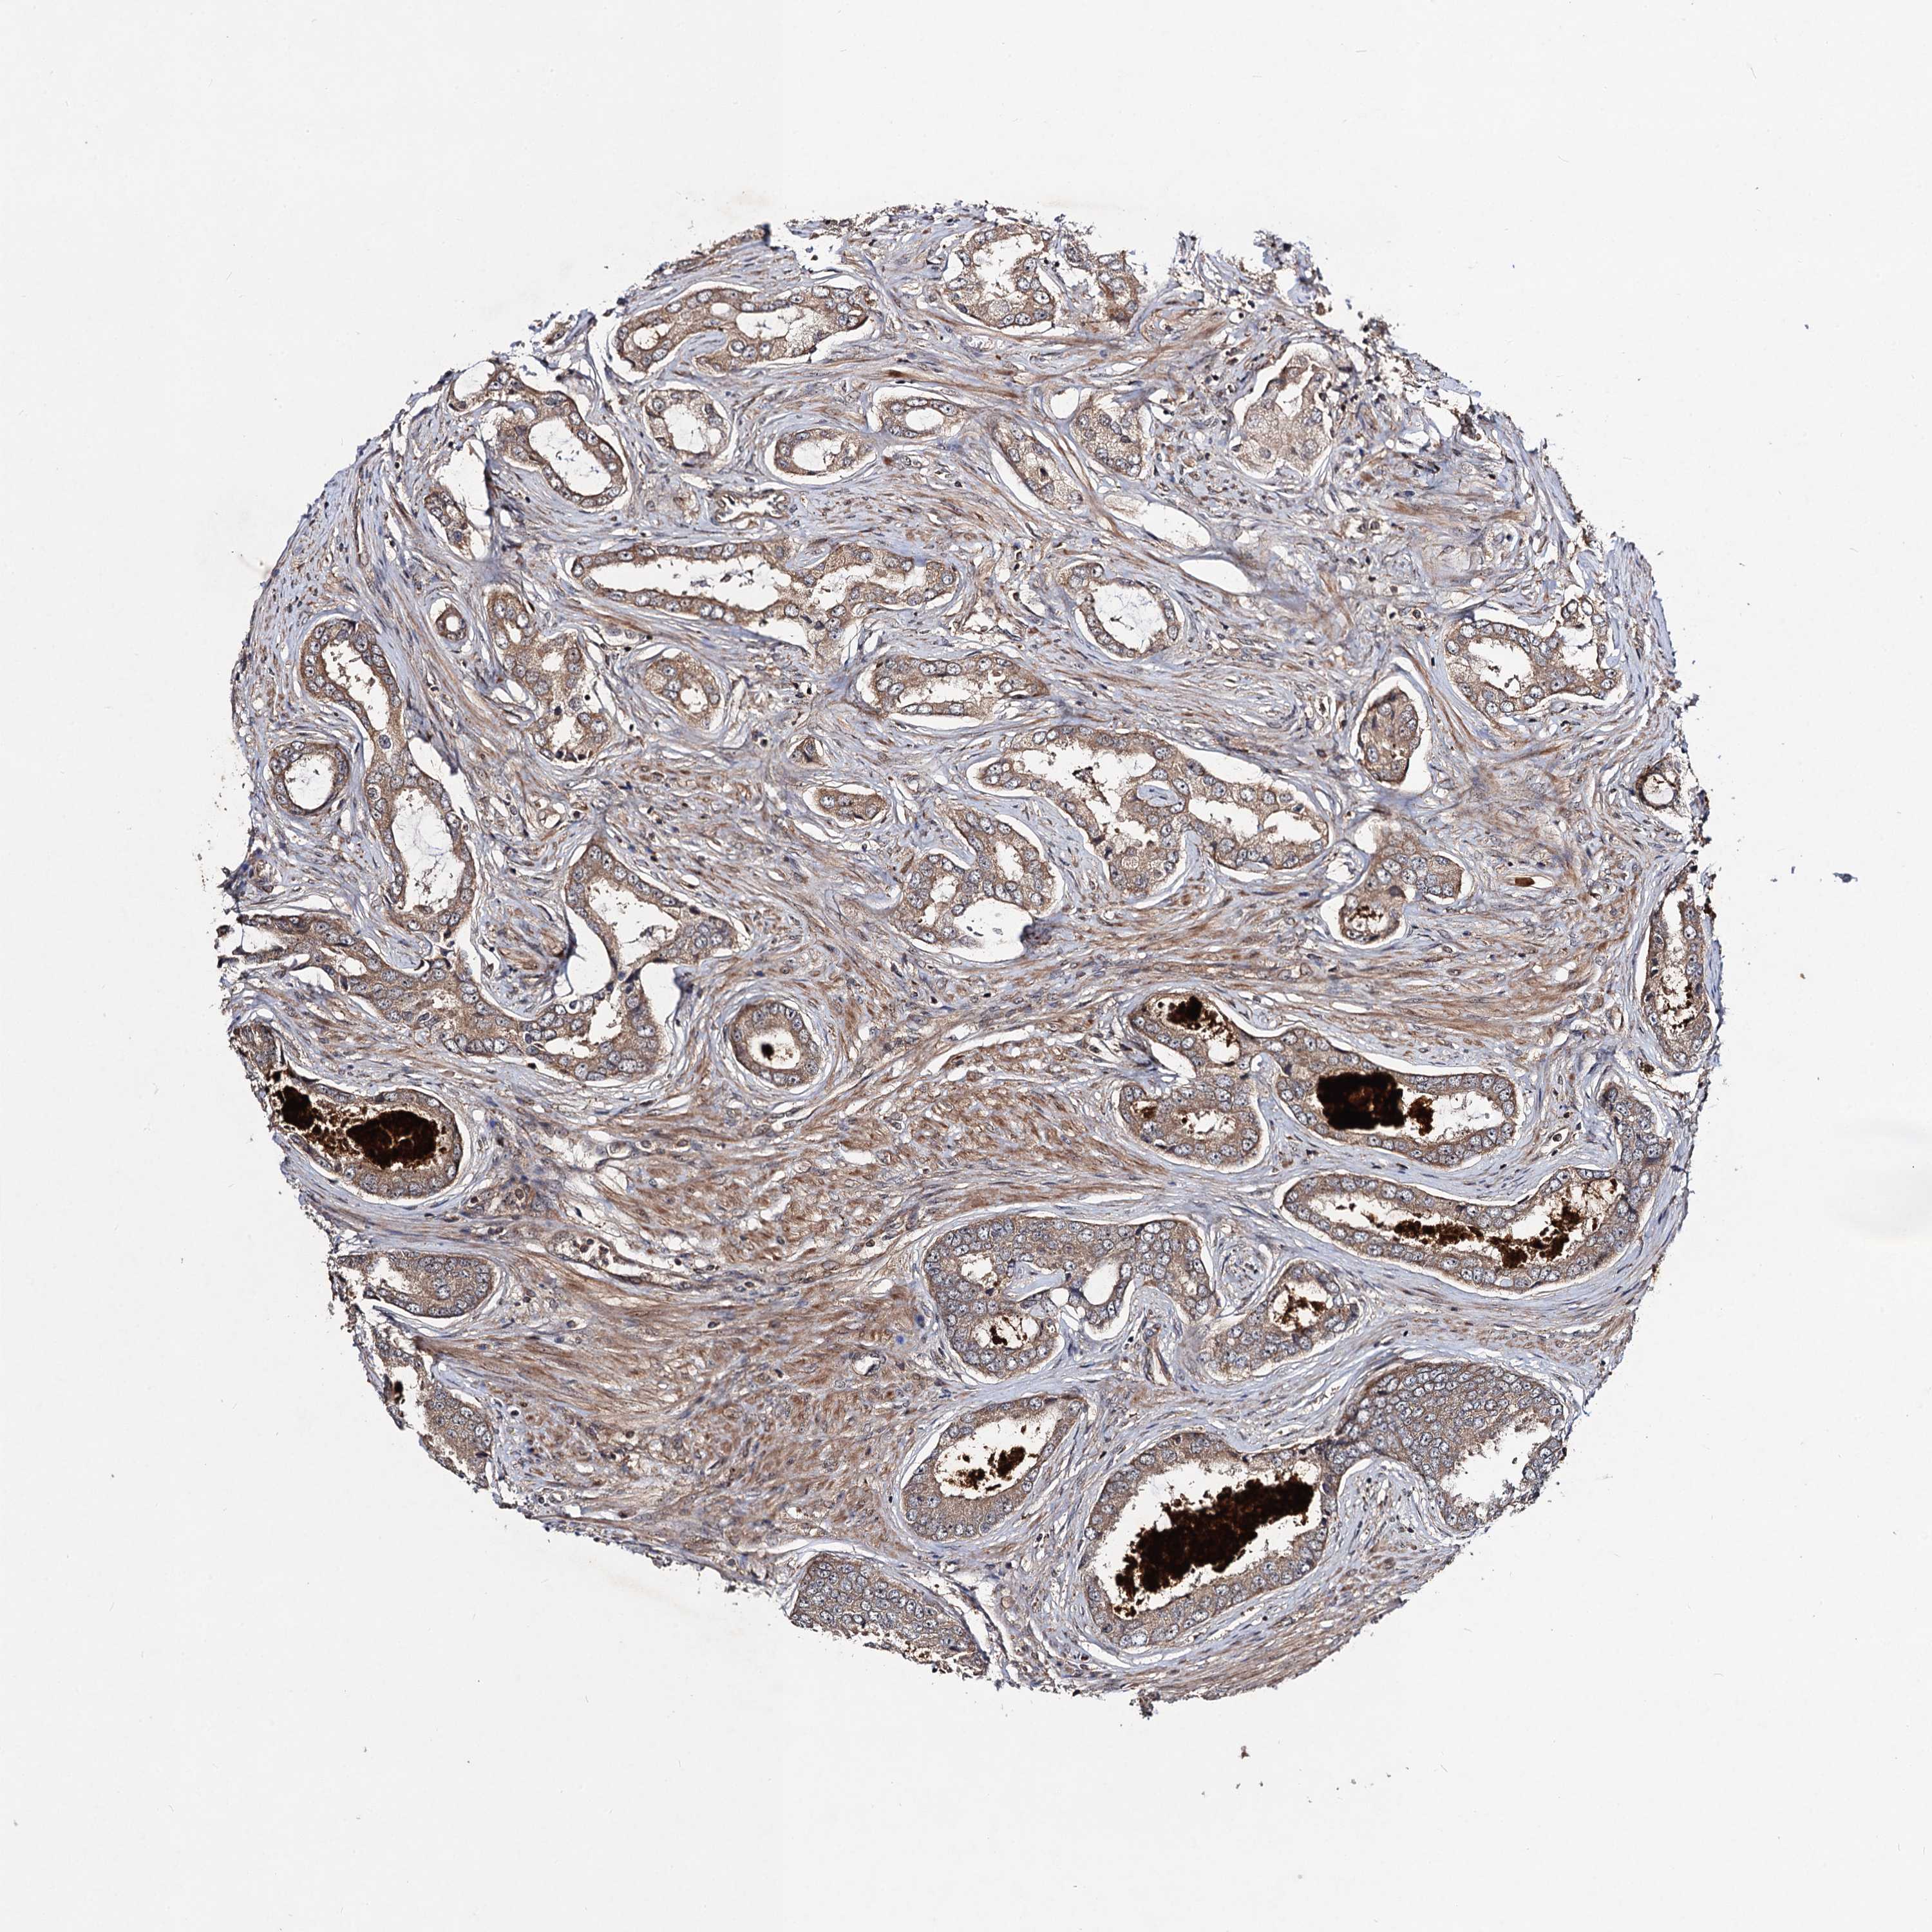

PROSTATE CANCER - Protein expressioni

A mouse-over function shows sample information and annotation data. Click on an image to view it in a full screen mode. Samples can be filtered based on level of antibody staining by selecting one or several of the following categories: high, medium, low and not detected. The assay and annotation is described here.

Antibody stainingi

Antibody staining in the annotated cell types in the current human tissue is reported as not detected, low, medium, or high, based on conventional immunohistochemistry profiling in selected tissues. This score is based on the combination of the staining intensity and fraction of stained cells.

Each image is clickable and will lead to virtual microscopy that enables deeper exploration of all samples and also displays staining intensity scores, fraction scores and subcellular localization as well as patient and tissue information for each sample.

Antibody HPA041507

Antibody HPA041599

Staining

High

Medium

Low

Not detected

Intensity

Strong

Moderate

Weak

Negative

Quantity

>75%

75%-25%

<25%

None

Location

Nuclear

Cytoplasmic/membranous

Cytoplasmic/membranous,nuclear

Adenocarcinoma, High grade

Adenocarcinoma, Low grade

Adenocarcinoma, NOS